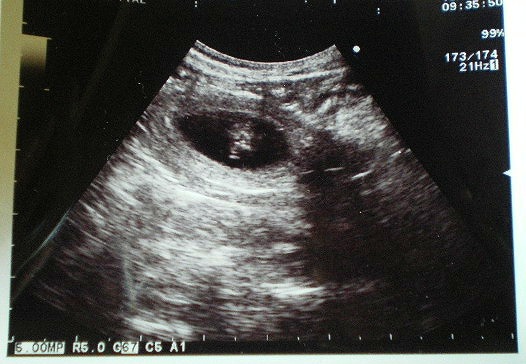

エコーの写真をしっかり頂いてきましたよ

上の方に黒く&丸く抜けている所の中の白くなっている所が子ももちゃんたち

今回のエコー検査では2頭の赤ちゃんが確認できたそうです。

まだ、全ての子は確認できないので、ちゃんとした数はまだわからないそうな。